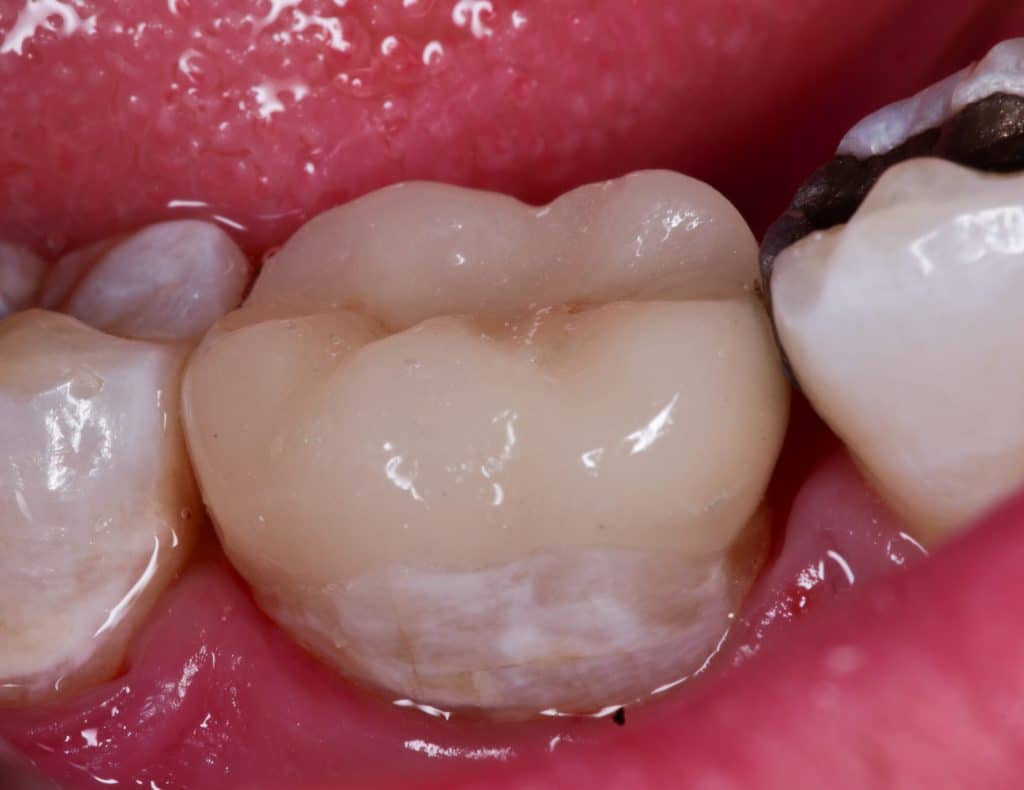

Cementation day , cementation with heated APx composite

Immediate result

Buccal view

Immediate after rubber dam removal

Immediate result , buccal view

Lingual view